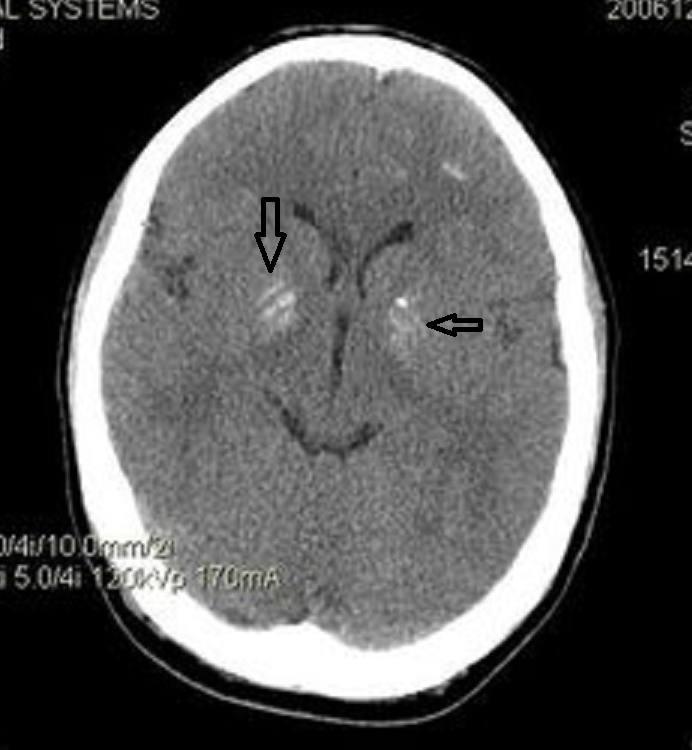

1、脑出血CT值40-45HU表示患者脑部存在较高密度的血肿,可能提示病情较严重,需结合临床情况综合判断。CT值是医学影像学中用于量化组织密度的单位,单位为亨氏单位(HU)。正常脑组织CT值约为25-45HU,而新鲜血液的CT值通常在40-80HU之间。

2、脑出血激活凝血系统后,血凝块形成,红细胞压积明显增加,CT上显示为高密度影,而腹腔出血往往为低密度的不凝血,原因为:呼吸运动、肠蠕动、腹膜的去纤维化纤维作用、创伤消耗凝血酶原等。一般不凝固的血液CT值约45HU,加上窗宽窗位和病变与邻近脏器密度对比的关系,腹腔出血往往显示为低密度。